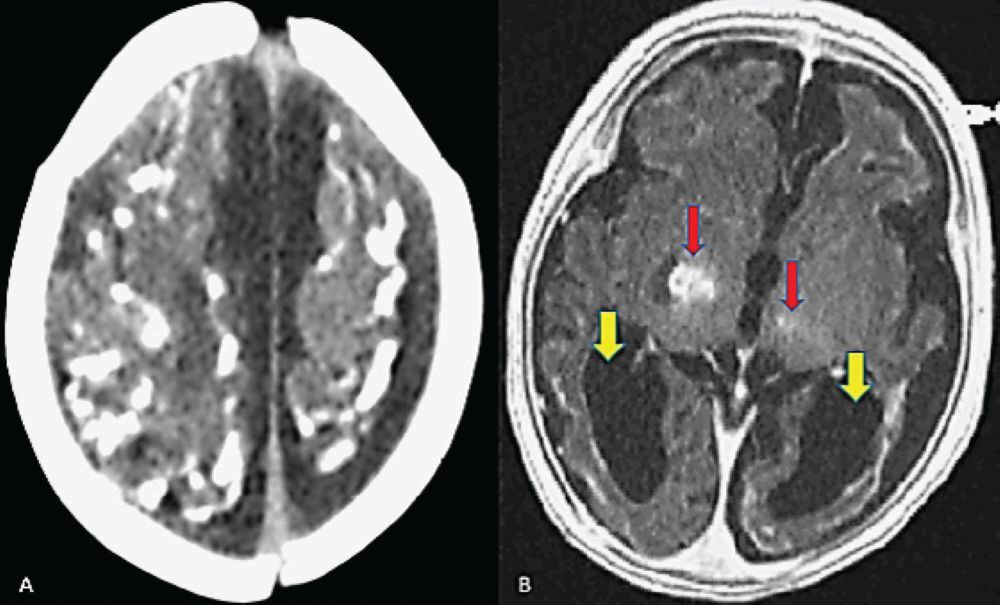

Cranial computed tomography done at the outside hospital shows diffuse cerebral calcifications. (Figure A) Cranial magnetic resonance imaging shows generalized parenchymal atrophy and dilation of the bilateral lateral ventricles with patent basal cisterns and coarse supratentorial calcifications involving the cortex, bilateral basal ganglia, and the vermis. (Figure B) She is intubated for airway protection and subsequently transferred to the pediatric intensive care unit for further evaluation and management.

A. Axial cranial CT of case patient showing generalized cortical calcifications with dilation of bilateral lateral ventricles. B. Axial cranial MRI of case patient showing generalized parenchymal atrophy and dilation of the bilateral lateral ventricles (yellow arrows) with patent basal cisterns and coarse supratentorial calcifications involving the cortex (red arrows), basal ganglia bilaterally, and the vermis. No midline shift was noted.